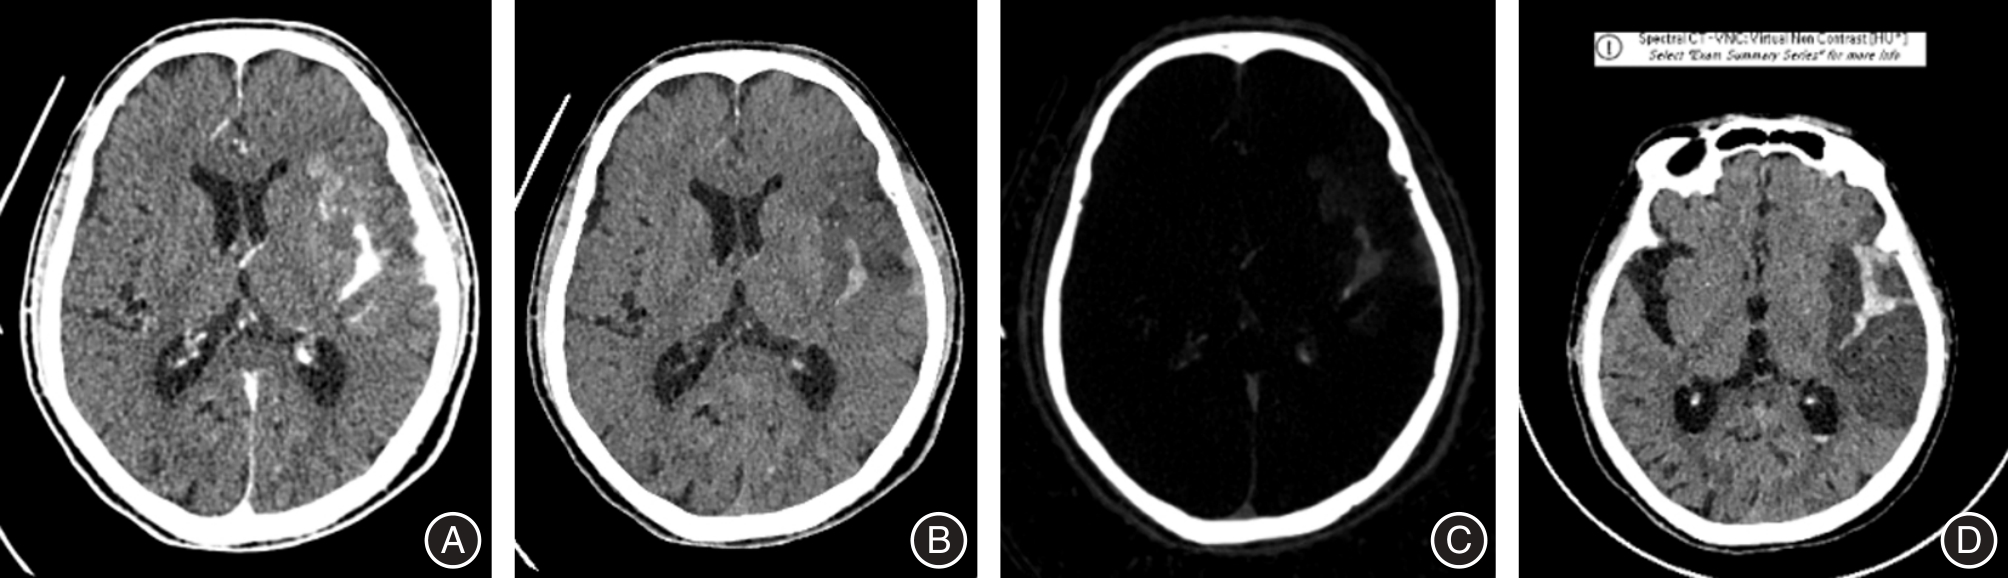

丁伟莉,王天宇,陈青,等. 急性缺血性卒中血管内介入治疗术后即刻及24 h双能CT检查对脑出血转化评估的作用[J]. 中国脑血管病杂志, 2023, 20(4):223-229.

郭爽,李清,吴芳,等. 双能CT在急性缺血性卒中血管内治疗术后早期脑出血与碘对比剂外渗鉴别诊断中的应用[J]. 首都医科大学学报, 2018, 39(2):173-177.

杨志安,闵小红,徐俏宇,等. 能谱CT虚拟平扫及水基图定量参数在诊断颅脑血管内治疗术后颅内出血的研究 [J]. 临床放射学杂志, 2024, 43(6): 872-877.

GULKO E, ALI S, GOMES W, et al. Differentiation of hemorrhage from contrast enhancement using dual-layer spectral CT in patients transferred for acute stroke[J]. Clin Imag, 2020, 69: 75-78. doi:10.1016/j.clinimag.2020.06.046

BERNSEN M L E, VEENDRICK P B, MARTENS J M, et al. Initial experience with dual-layer detector spectral CT for diagnosis of blood or contrast after endovascular treatment for ischemic stroke[J]. Neuroradiol, 2022, 64(1): 69-76. doi:10.1007/s00234-021-02736-5

RIEDERER I, FINGERLE A A, ZIMMER C, et al. Potential of dual-layer spectral CT for the differentiation between hemorrhage and iodinated contrast medium in the brain after endovascular treatment of ischemic stroke patients[J]. Clin Imaging, 2021, 79: 158-164. doi:10.1016/j.clinimag.2021.04.020